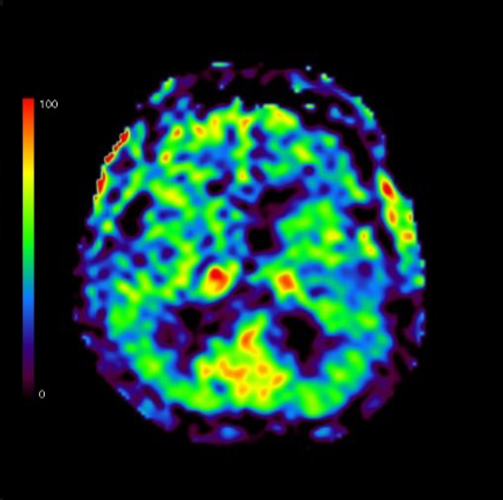

内臓脂肪CT

お臍の位置で画像を数枚撮影して、内臓脂肪と皮下脂肪の面積を測定します。生活習慣病のリスクが高まる内臓脂肪型肥満を判定できます。検査時間が短く撮影もお臍の位置の数枚だけなので被ばくも少ないです。

内臓脂肪が多いと心疾患や脳血管疾患が起こりやすくなります。内臓脂肪型肥満は隠れ肥満とも言われ痩せている人でも内臓に脂肪が蓄積し肥満となることがあります。

CT検査Q&A

赤:内臓脂肪面積

青:皮下脂肪面積

内臓脂肪型肥満の方の画像になります。青の皮下脂肪に比べて赤の内臓脂肪面積の方が広いことがわかります。